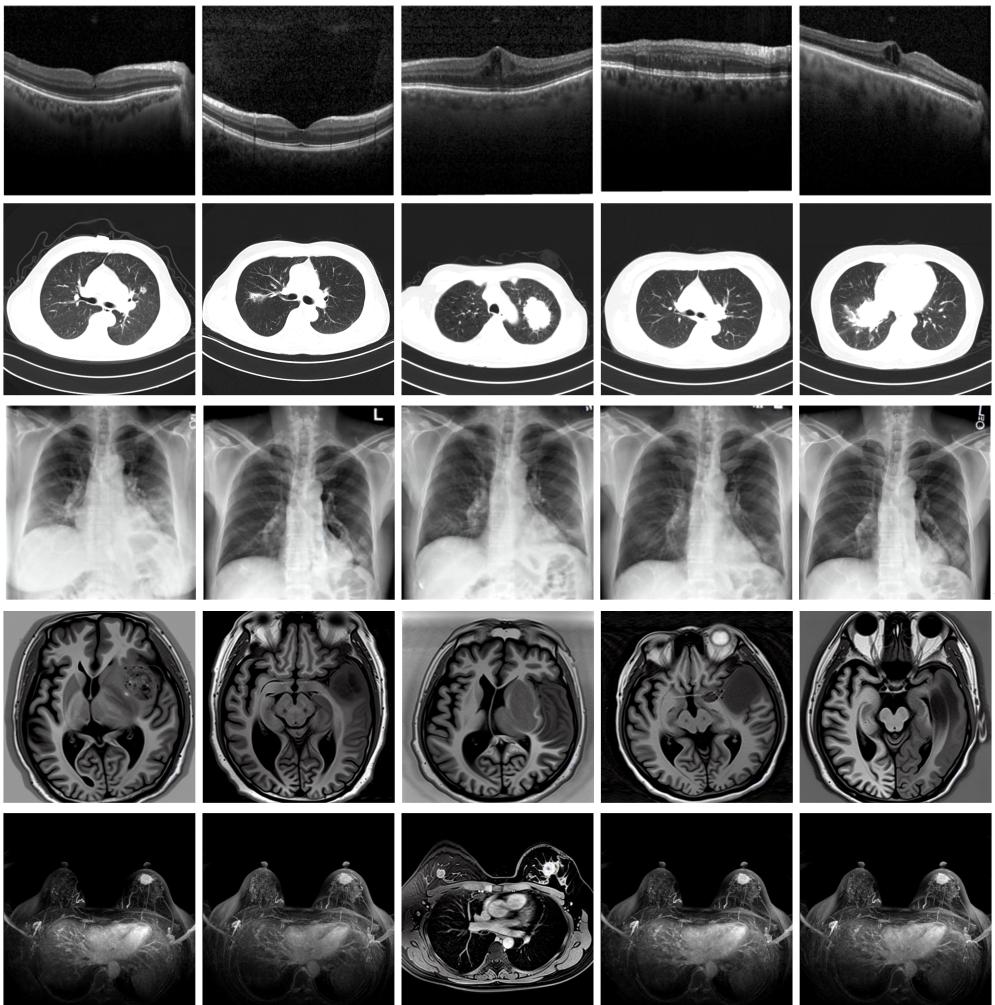

圖為由MINIM生成的高質(zhì)量醫(yī)學(xué)合成圖像(受訪(fǎng)者供圖)

“目前公開(kāi)的醫(yī)學(xué)影像數(shù)據(jù)非常有限,我們建立的生成式模型有望解決訓(xùn)練數(shù)據(jù)不夠的問(wèn)題?!北本┐髮W(xué)未來(lái)技術(shù)學(xué)院助理研究員王勁卓說(shuō),研究團(tuán)隊(duì)利用多種器官在CT、X光、磁共振等不同成像方式下的高質(zhì)量影像文本配對(duì)數(shù)據(jù)進(jìn)行訓(xùn)練,最終生成海量的醫(yī)學(xué)合成影像,其在圖像特征、細(xì)節(jié)呈現(xiàn)等多方面都與真實(shí)醫(yī)學(xué)圖像高度一致。

實(shí)驗(yàn)結(jié)果顯示,MINIM生成的合成數(shù)據(jù)在醫(yī)生主觀(guān)評(píng)測(cè)指標(biāo)和多項(xiàng)客觀(guān)檢驗(yàn)標(biāo)準(zhǔn)方面達(dá)國(guó)際領(lǐng)先水平,在臨床應(yīng)用中具有重要參考價(jià)值。在真實(shí)數(shù)據(jù)基礎(chǔ)上,使用20倍合成數(shù)據(jù)在眼科、胸科、腦科和乳腺科的多個(gè)醫(yī)學(xué)任務(wù)準(zhǔn)確率平均可提升12%至17%。